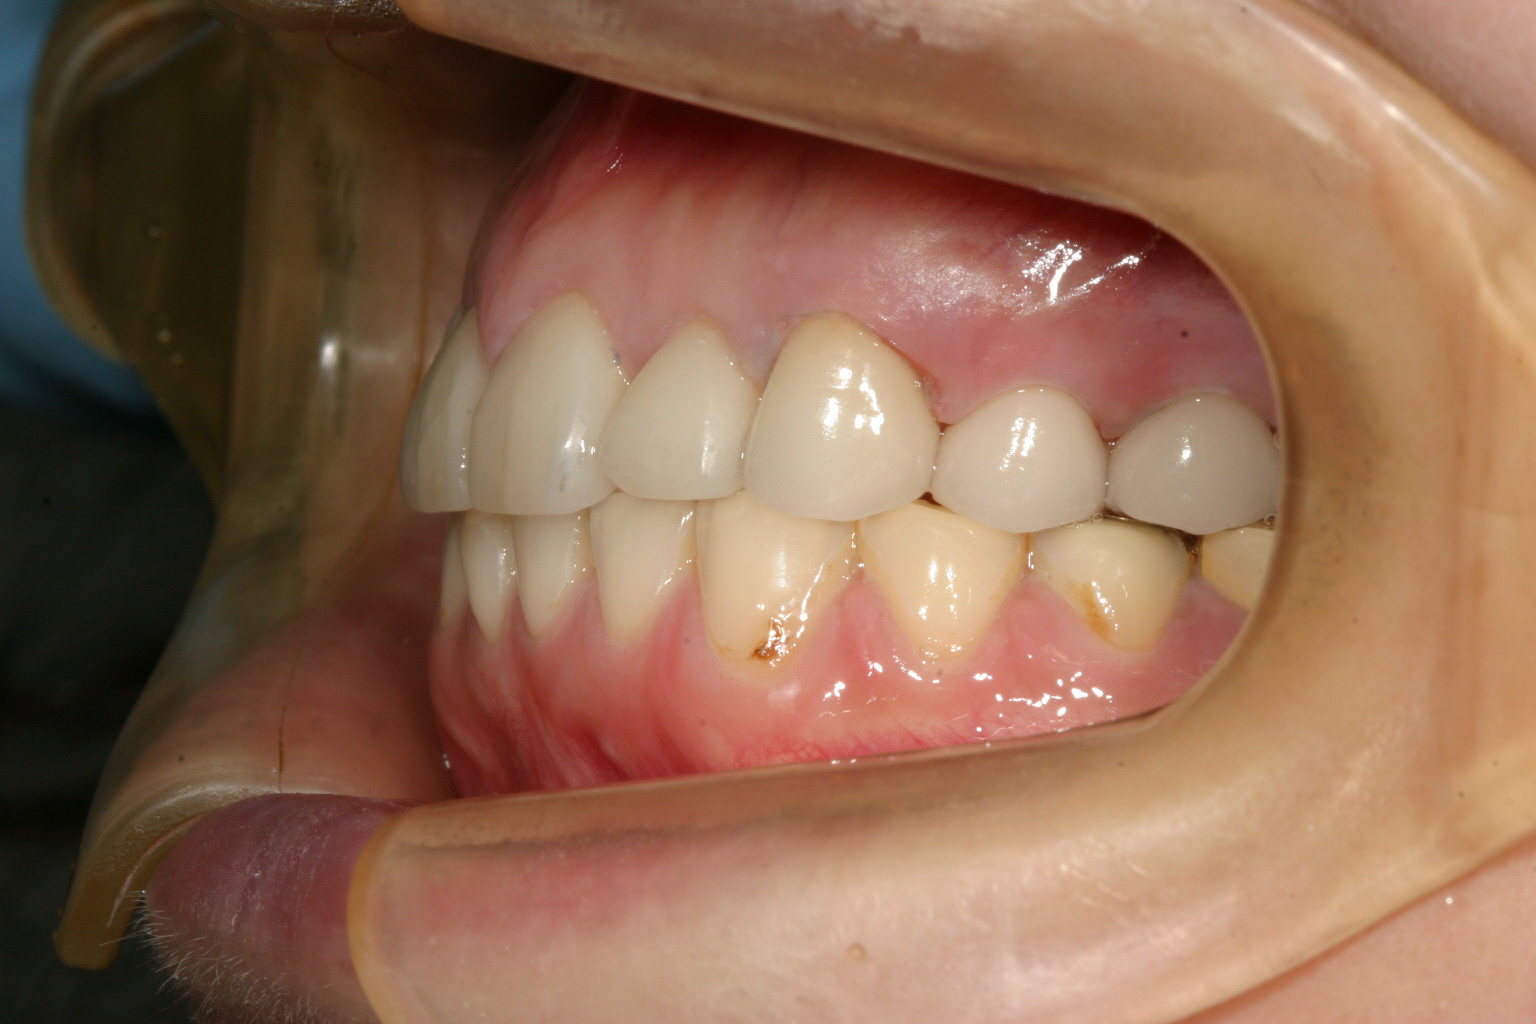

横からの咬み合わせも綺麗に改善しました。

オーバーバイトも綺麗にいい感じになっています。